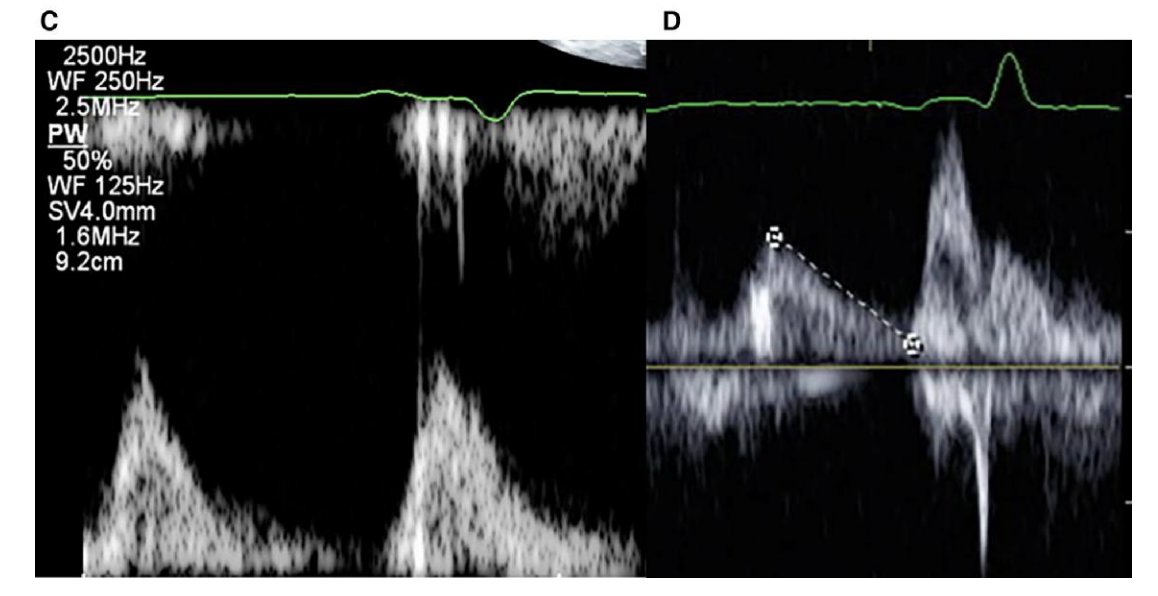

BBp corrected interatrial block with marked reduction of PWD compared to sinus and RAAp ⚡️